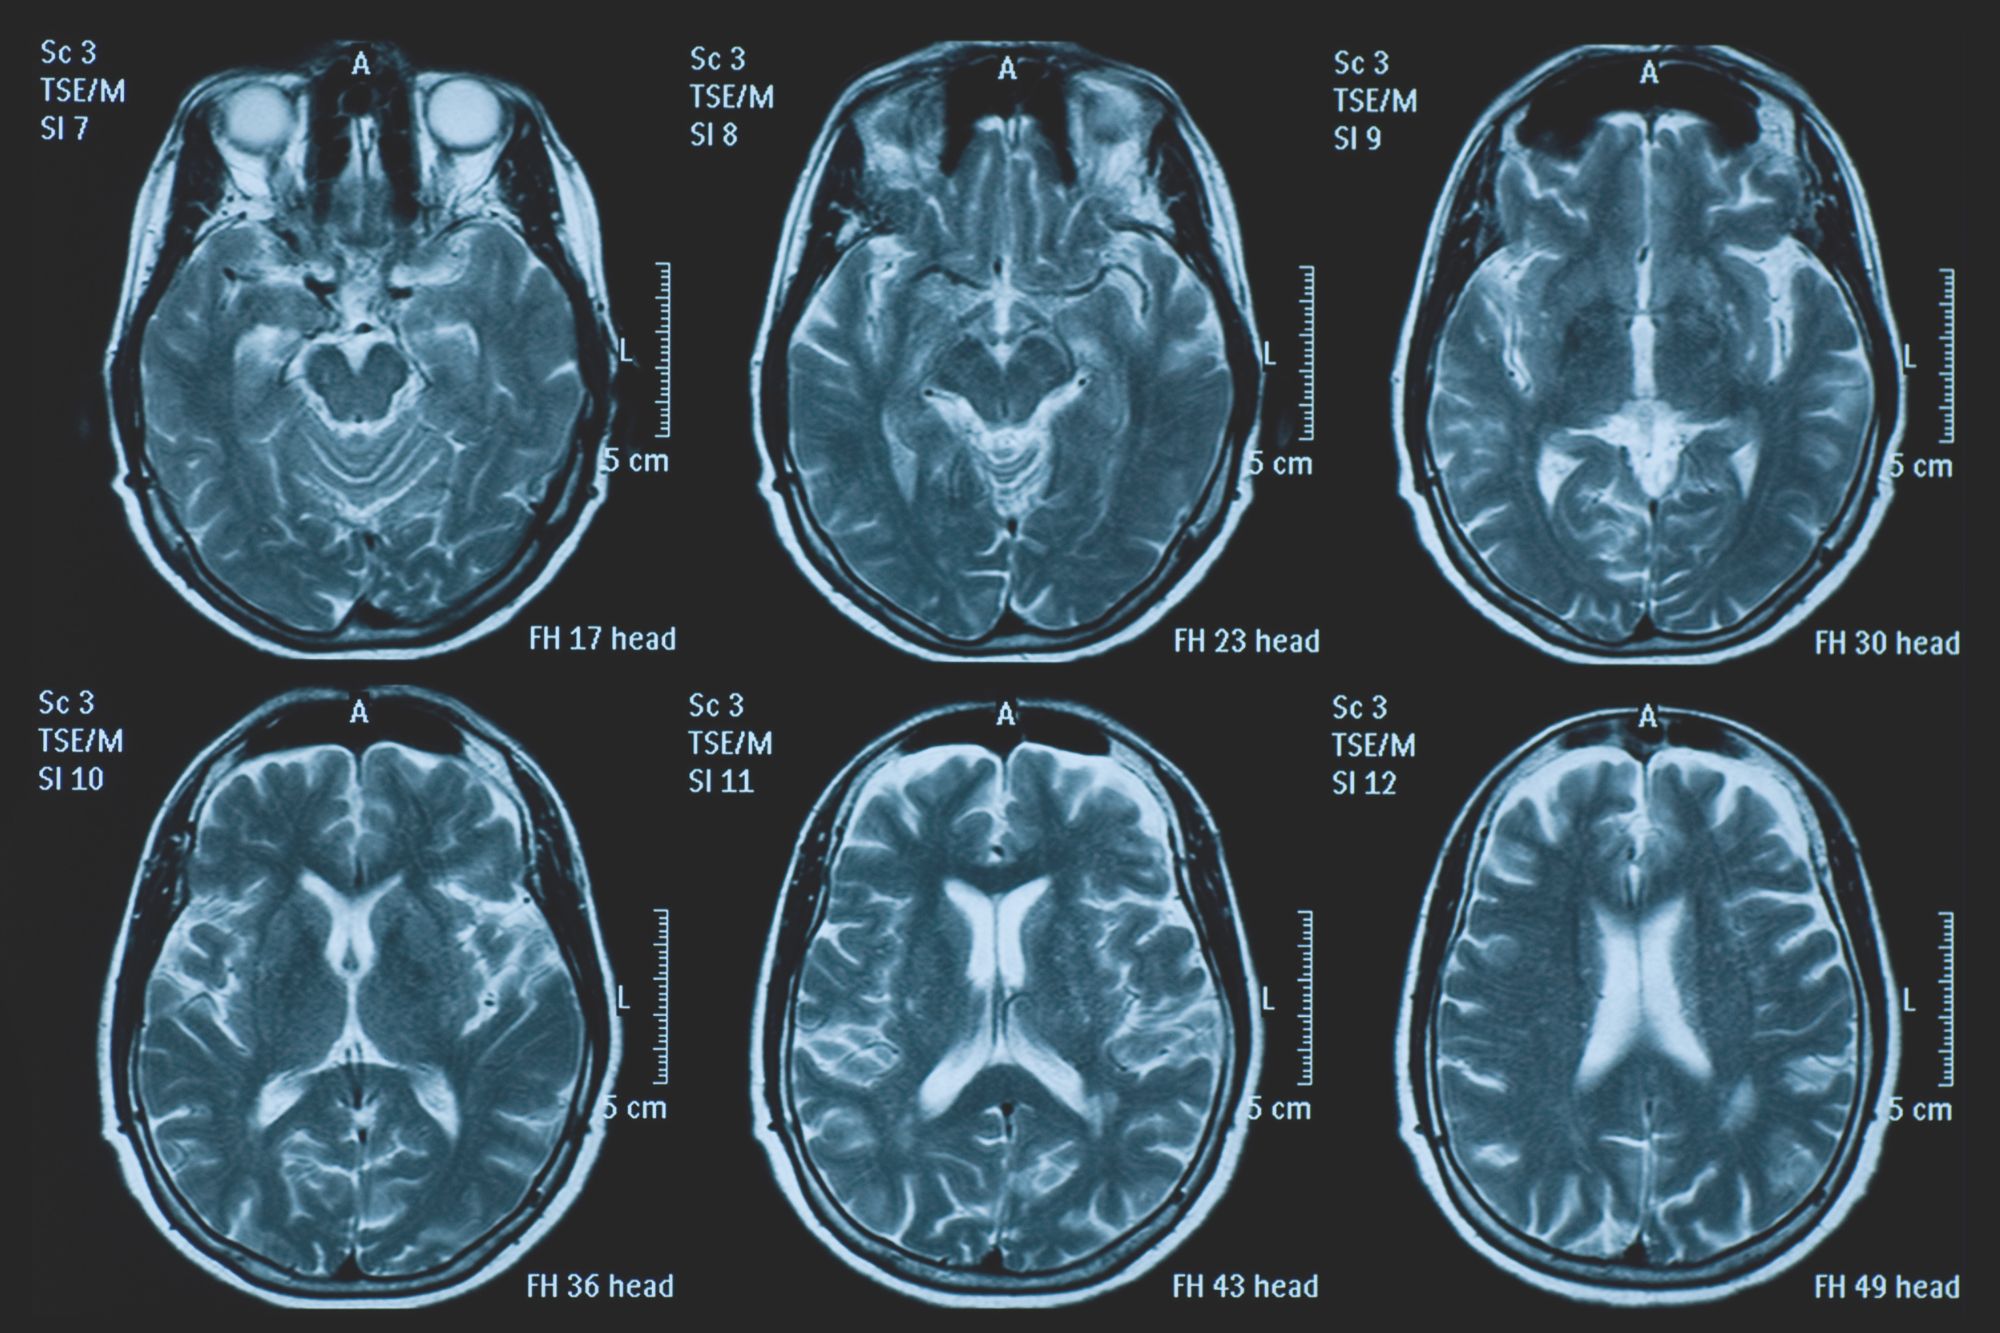

La pandemia ha invecchiato il nostro cervello. A rilevarlo è una ricerca condotta dagli esperti dell’Università di Nottingham, e pubblicata su Nature Communications, secondo la quale la diffusione del virus da Covid-19 – e tutto ciò che ne è conseguito – avrebbe avuto un impatto di non poco conto sulla salute del nostro cervello. I—Mondo

Impatto del Covid-19 sul cervello, i ricercatori: “Invecchiato di 5 mesi”